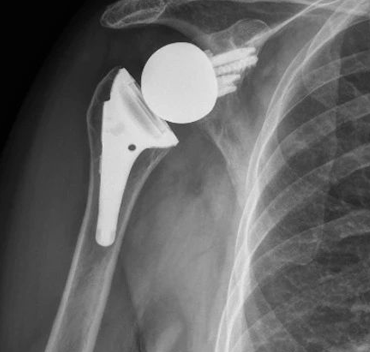

Great weeks worth of joint replacement surgeries. Anatomic , reverse, & before/after of a revision reverse. It's not work when you're having fun! Have a great weekend!

Money talks. You can't argue with this function. This is a 1 yr follow up of a @enovismedtech reverse shoulder arthroplasty. Gotta love when you can see the patient's